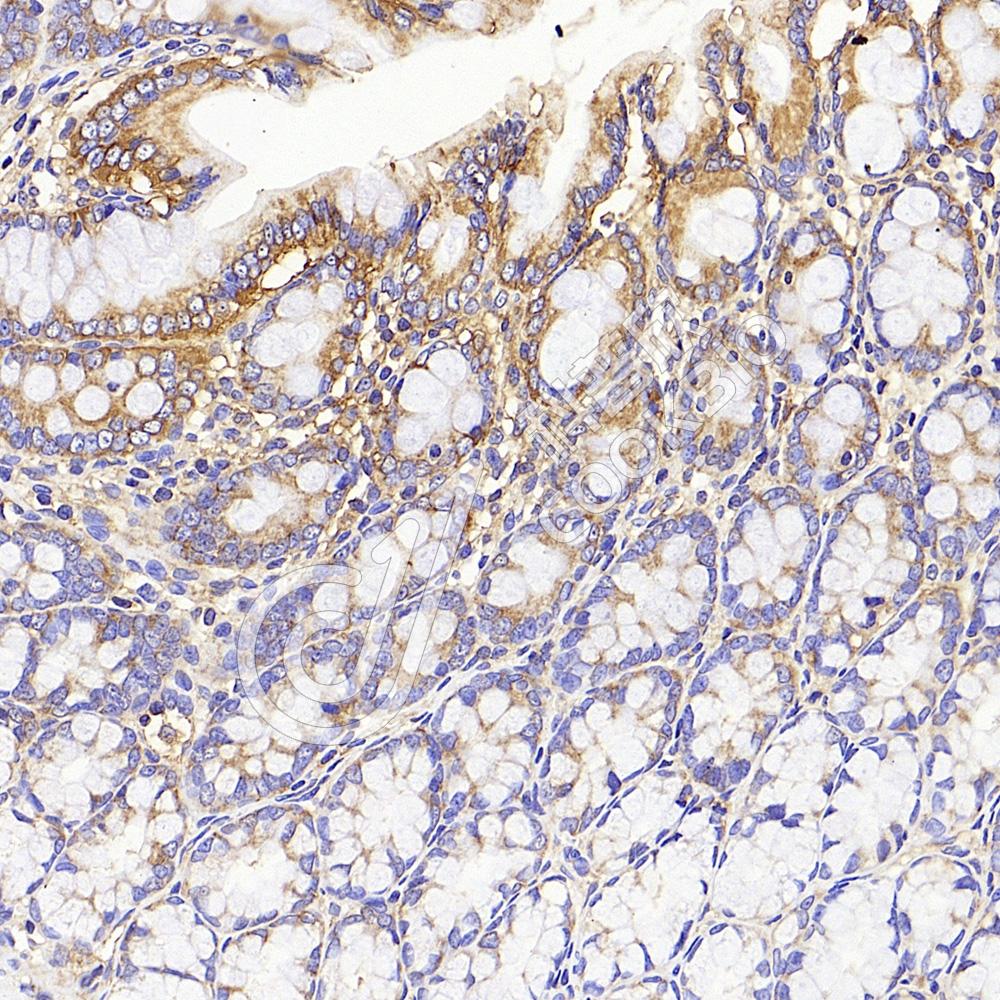

IHC检测CD13蛋白(货号 K134068).

样品: 大鼠结肠, 4%多聚甲醛 (货号KSG1101) 固定12-24小时.

抗原修复: 柠檬酸抗原修复液(干粉, pH 6.0) (KSG1201), 98℃, 20分钟.

—抗: 1: 1300稀释, 4℃ 孵育过夜.

二抗: S-vision免疫组化多聚二抗(山羊抗兔),即用型 (货号KB3906), 室温孵育20分钟.